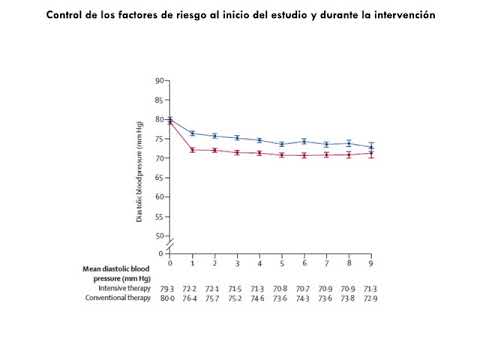

Control de la presión arterial y riesgo de mortalidad en una cohorte de pacientes adultos mayores: estudio Berlin. Dr. Agustín Padula. Residencia de Cardiología. Hospital C. Argerich. Buenos Aires